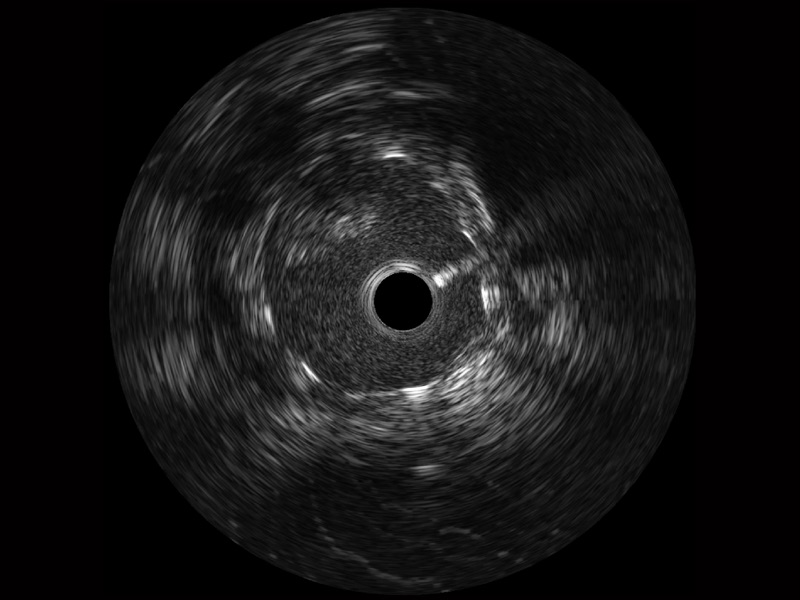

狗万官方网站宽频IVUS图像

对比传统IVUS导管成像,狗万官方网站宽频IVUS图像的近场支架梁显影更细腻,远场中膜外血管仍清晰可辨,兼顾远中近,兼顾分辨力与穿透深度